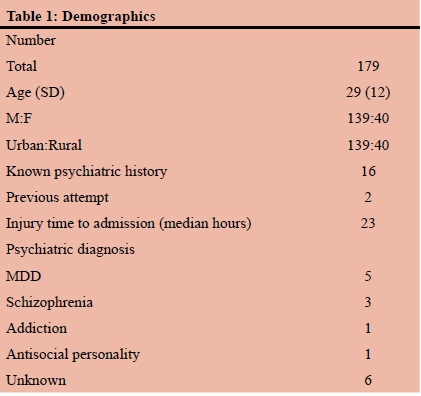

RESULTS: During the five-year study period, a total of 179 patients were included. The mean age was 29 years (SD12) and there were 139 (77%) males and 40 (23%) females. Of these, 16 had a previously established psychiatric diagnosis and two had a prior history of having sustained self-harm. The previously diagnosed psychiatric illnesses included mood dysphoria disorders (5), schizophrenia (3), substance abuse and dependency (1), anti-social personality disorder (1) and unspecified (6). The mechanism was penetrating trauma in 47 (26%). The penetrating mechanisms included stab wounds (SW) in 33, gunshot wounds (GSW) in 10, broken glass in 2 and a single impalement. Blunt mechanisms accounted for the remaining 131 (73%) injuries. The most common mechanism of blunt self-harm was hanging in 101 patients. This was followed by vehicular related trauma (8), jumping in front of a train (1) and jumping from a height (1). In 17 patients the exact mechanism of the blunt trauma was unclear. There was no statistical difference in the mechanism of injury between male and female patients. There were 38 (28%) men and 9 (23%) women who sustained a penetrating injury and there were 100 (72%) male and 31 (78%) female patients who had a blunt mechanism of injury. A total of 53 CT scans were obtained, 40 chest X-rays, 9 abdominal X-rays and 2 ultrasounds. There were 113 neck injuries, 68 head injuries, 24 abdominal injuries, 15 upper limb and 15 lower limb injuries and four facial injuries. A total of 32 operations were performed. These included laparotomy (14), neck exploration (5), tracheostomy (4). A total of 22 patients developed a complication

Demographics and presenting physiology

During the five-year study period, a total of 179 patients sustained self-harm and were managed by the PMTS. The mean age was 29 years (SD12) and there were 139 (77%) males and 40 (23%) females. Of these, 16 had a previously established psychiatric diagnosis and two had prior histories of having sustained self-harm. The previously diagnosed psychiatric illnesses included MDD (5), schizophrenia (3), substance abuse and dependency (1), anti-social personality disorder (1) and unspecified (6). In the patients who attempted to hang themselves, 60.9% had consumed alcohol just prior to the incident. There were 139 patients from the city of Pietermaritzburg and 40 from the rural areas of western KZN. Table 1 summarizes the demographics of the cohort. Table 2 summarizes the presenting physiology of the patient cohort.